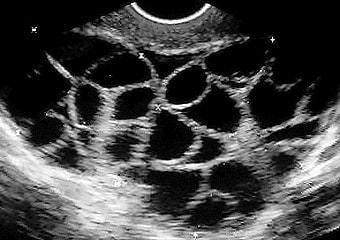

Можно ли проводить искусственное оплодотворение при СПКЯ? Процедура ЭКО является сложным процессом. У женщин с историей поликистоза яичников есть определенные особенности, которые могут повлиять на проведение вспомогательной репродуктивной технологии:

- высокий запас яйцеклеток;

- низкий процент эмбрионов хорошего качества;

- низкие показатели оплодотворения;

- повышенный риск гиперстимуляции яичников;

ЭКО также возможно при сочетании СПКЯ с другими формами бесплодия, такими как патологии маточных труб или их отсутствие, мужской фактор и другие. Для женщин с поликистозом яичников разрабатывается индивидуальный протокол ЭКО и подбираются гормональные препараты, необходимые для стимуляции и поддержания беременности. Врачи-репродуктологи относят таких пациенток к группе риска, так как их организм может непредсказуемо реагировать на гормональную терапию, что может потребовать экстренной корректировки назначений.

Женщины с диагнозом синдром поликистозных яичников находятся под особым наблюдением репродуктологов во время стимуляции. Стимуляция яичников может быть рискованной, так как существует вероятность гиперстимуляции, что является серьезным осложнением после процедуры ЭКО.